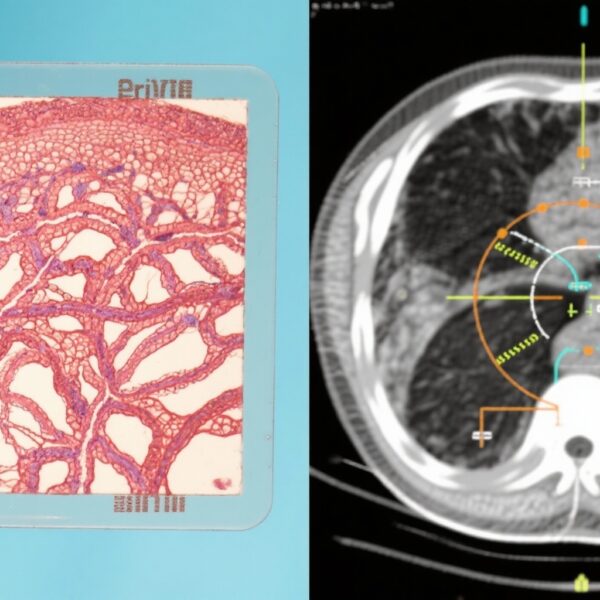

Ung thư tuyến tiền liệt di căn nhạy cảm với hormon (mHSPC) đại diện cho tình trạng bệnh tiến triển, trong đó ung thư tuyến tiền liệt đã lan ra ngoài tuyến nhưng vẫn đáp ứng với các liệu pháp làm giảm mức độ androgen. Liệu pháp tước hormon (ADT) đã là nền tảng của điều trị; tuy nhiên, sự kháng thuốc và tiến triển vẫn là những thách thức chính. Antigen cụ thể tuyến tiền liệt (PSA) là một dấu ấn sinh học được sử dụng rộng rãi để theo dõi hoạt động của ung thư tuyến tiền liệt, và sự giảm PSA sớm đã được chứng minh tương quan với sự sống sót cải thiện ở bệnh nhân mHSPC. Enzalutamide, một chất ức chế thụ thể androgen mạnh, đã cho thấy hiệu quả trong ung thư tuyến tiền liệt di căn kháng androgen và gần đây hơn trong tình trạng nhạy cảm với hormon khi kết hợp với ADT. Tuy nhiên, dữ liệu về mối quan hệ giữa động lực PSA và kết quả lâm sàng với enzalutamide cộng với ADT trong mHSPC còn hạn chế, thúc đẩy phân tích phụ này của thử nghiệm ARCHES.

Thiết kế nghiên cứu

Thử nghiệm ARCHES là một thử nghiệm lâm sàng ngẫu nhiên, mù đôi, giai đoạn 3 đa quốc gia, đăng ký 1150 nam giới mắc mHSPC từ tháng 3 năm 2016 đến tháng 1 năm 2018. Các bệnh nhân đủ điều kiện được ngẫu nhiên hóa 1:1 để nhận enzalutamide (160 mg mỗi ngày) cộng với ADT hoặc giả dược cộng với ADT. Bệnh nhân được phép sử dụng ADT trước đó từ 3 đến 6 tháng trước khi đăng ký. Các điểm cuối chính bao gồm thời gian sống không tiến triển theo hình ảnh (rPFS) và thời gian sống tổng thể (OS). Phân tích phụ này chia bệnh nhân thành các nhóm dựa trên mức độ PSA khi vào nghiên cứu, tập trung vào những người đã tiếp xúc với ADT trước đó. Sự giảm PSA sau 6 tháng, đặc biệt là đạt được PSA không phát hiện được (<0.2 ng/mL), được liên kết với kết quả rPFS và OS. Các thời gian theo dõi bao gồm thời gian trung bình 14.4 tháng và 44.6 tháng cho các phân tích giữa kỳ và cuối cùng, tương ứng.